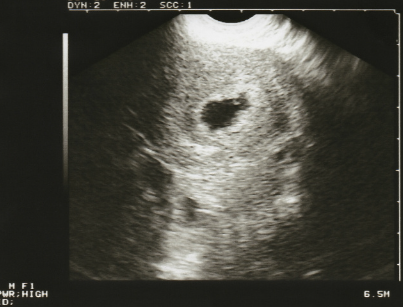

아기의 심장박동을 확인할 수 있다.

임신 6주에서 9주 사이에는 아기의 심장박동을 확인할 수 있다. 만약 네가 심장박동을 확인한다면, 너는 정상적인 임신을 확인할 수 있다.

만약 네가 확인할 수 없다면, 너는 다음 주에 검진을 받을 때까지 그것을 봐야 한다.